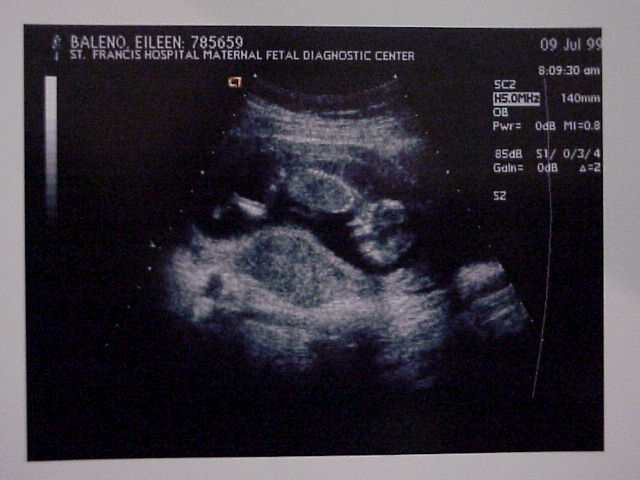

Close up of the baby.